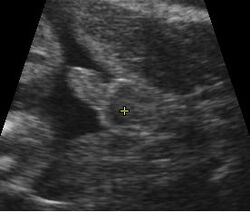

A gestational sac can be reliably seen on transvaginal ultrasound by 5 weeks' gestational age (approximately 3 weeks after ovulation). The embryo should be seen by the time the gestational sac measures 25 mm, about five-and-a-half weeks.[10] The heartbeat is usually seen on transvaginal ultrasound by the time the embryo measures 5 mm, but may not be visible until the embryo reaches 19 mm, around 7 weeks' gestational age.[5][11][12] Coincidentally, most miscarriages also happen by 7 weeks' gestation. The rate of miscarriage, especially threatened miscarriage, drops significantly after normal heartbeat is detected, and after 13 weeks.[13]

Contents in the cavity of the uterus seen at approximately 5 weeks of gestational age